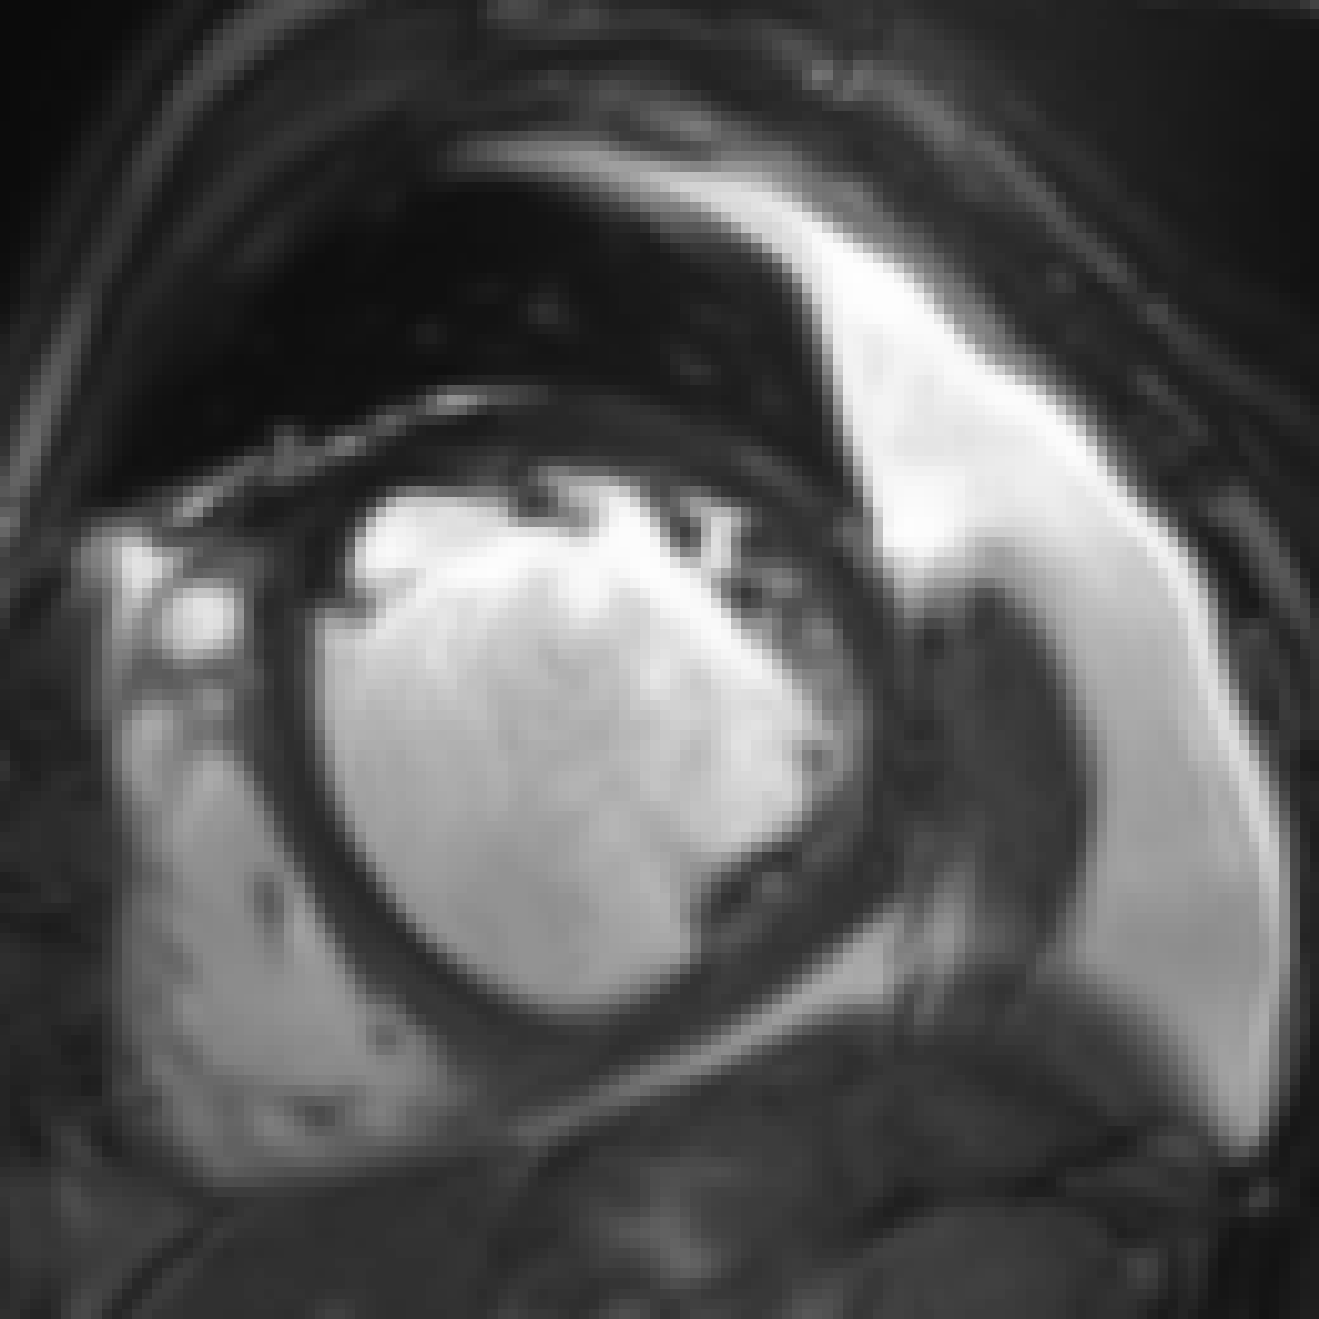

Figure 9: Zoomed-in images of synthesis results in scans of two different patients (one example per row) using neonatal brain MRIs from the dHCP dataset. Slice spacing was improved from 222 to 0.29 mmtimes0.29millimeter0.29\text{\,}\mathrm{mm} by synthesizing six intermediate slices (second to penultimate columns). For this, latent space encodings of the two neighboring slices (first and last column) were combined using their convex combination. α𝛼\alpha denotes the mixing coefficient as specified in Equation 1. Bounding boxes focus on anatomical variations between images in a row. Note that a small cross-fade artifact appears in the bright area of the fourth (α=3/7𝛼37\alpha=\nicefrac{{3}}{{7}}) and fifth (α=4/7𝛼47\alpha=\nicefrac{{4}}{{7}}) image in the second row.

Slice Synthesis: Qualitative evaluation of the proposed approach on neonatal brain MRI with reveals that generated slices using a convex combination of neighboring slice encodings, comprise a smooth anatomical transition between adjacent slices. Examples depicted in Figure 9 show upsampling performance of proposed method for neighboring slices with large anatomical variations. In the depicted figures slice spacing was improved from 222 to 0.29 mmtimes0.29millimeter0.29\text{\,}\mathrm{mm} by synthesizing six intermediate slices using latent space encodings of the two neighboring slices.